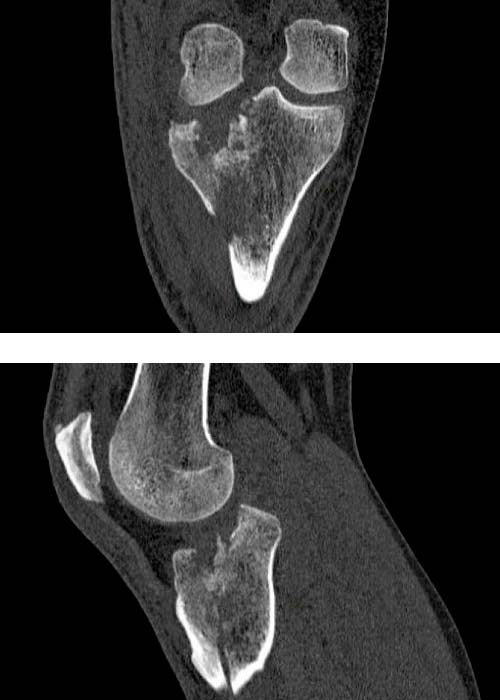

Se realiza estudio con pruebas complementarias (radiografías y TAC):

En TAC se objetiva una fractura conminuta de la meseta tibial con hundimiento del platillo tibial anterolateral con líneas de fractura diafisarias anteriores, mediales y posteriores.

Diagnosticado de fractura meseta tibial según la clasificación de Schatzker, tipo II (combinación de hundimiento y separación) y tipo VI con disociación de la metáfisis y la diáfisis.